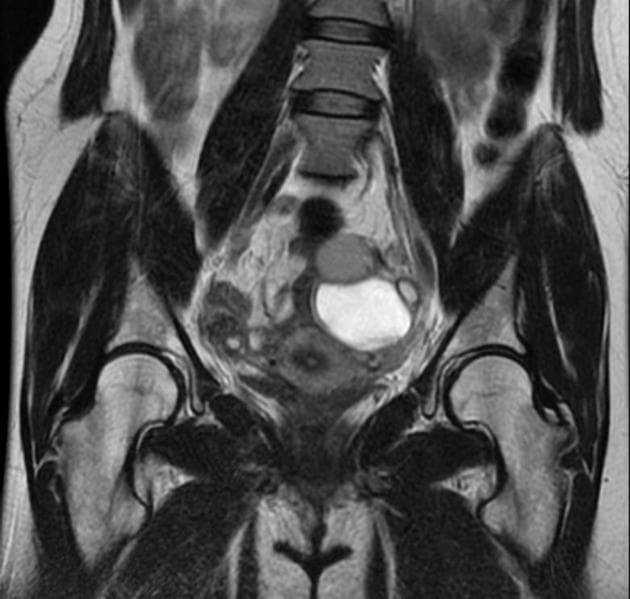

Coronal T2

MRI•Coronal T2•1 Img

- Tổn thương dạng nang lớn ở vùng chậu bụng bên phải, trên cộng hưởng từ (MRI) tổn thương này tăng tín hiệu ở chuỗi xung T1 và T2, có vách ngăn nội tại.

- "U lạc nội mạc tử cung thường biểu hiện là các nang buồng trứng đơn hoặc đa ngăn, có tăng tín hiệu đồng nhất trên cả chuỗi xung T1 và T2 do chứa sản phẩm máu mạn tính."

- "Dấu hiệu chấm tối trên T2 (T2 shading) trong lòng nang là đặc điểm điển hình của u lạc nội mạc, do lắng đọng hemosiderin đậm đặc."

- "Vách ngăn nội tại và dày thành nang dạng nốt cho thấy tình trạng mạn tính hoặc nguy cơ chuyển ác, cần theo dõi sát."

U lạc nội mạc tử cung, còn gọi là 'nang sô cô la', là một dạng lạc nội mạc tử cung khi mô nội mạc tử cung lạc chỗ bám vào buồng trứng và xuất huyết theo chu kỳ. Trên cộng hưởng từ (MRI), u lạc nội mạc thường có tín hiệu tăng trên cả chuỗi T1 và T2 do chứa máu cũ. Hiện tượng 'mờ tín hiệu trên T2' (T2 shading) – khi tín hiệu giảm dần trên hình T2 – rất gợi ý cho chẩn đoán u lạc nội mạc. Các chẩn đoán phân biệt bao gồm nang buồng trứng xuất huyết, u nang tuyến mề và u tuyến nang nhầy. Tuy nhiên, tín hiệu T1 tăng rõ rệt và vách ngăn nội tại làm tăng khả năng u lạc nội mạc. Chẩn đoán chính xác rất quan trọng để định hướng điều trị, bao gồm điều trị nội tiết hoặc phẫu thuật cắt bỏ, đặc biệt ở bệnh nhân vô sinh hoặc đau vùng chậu mạn tính.